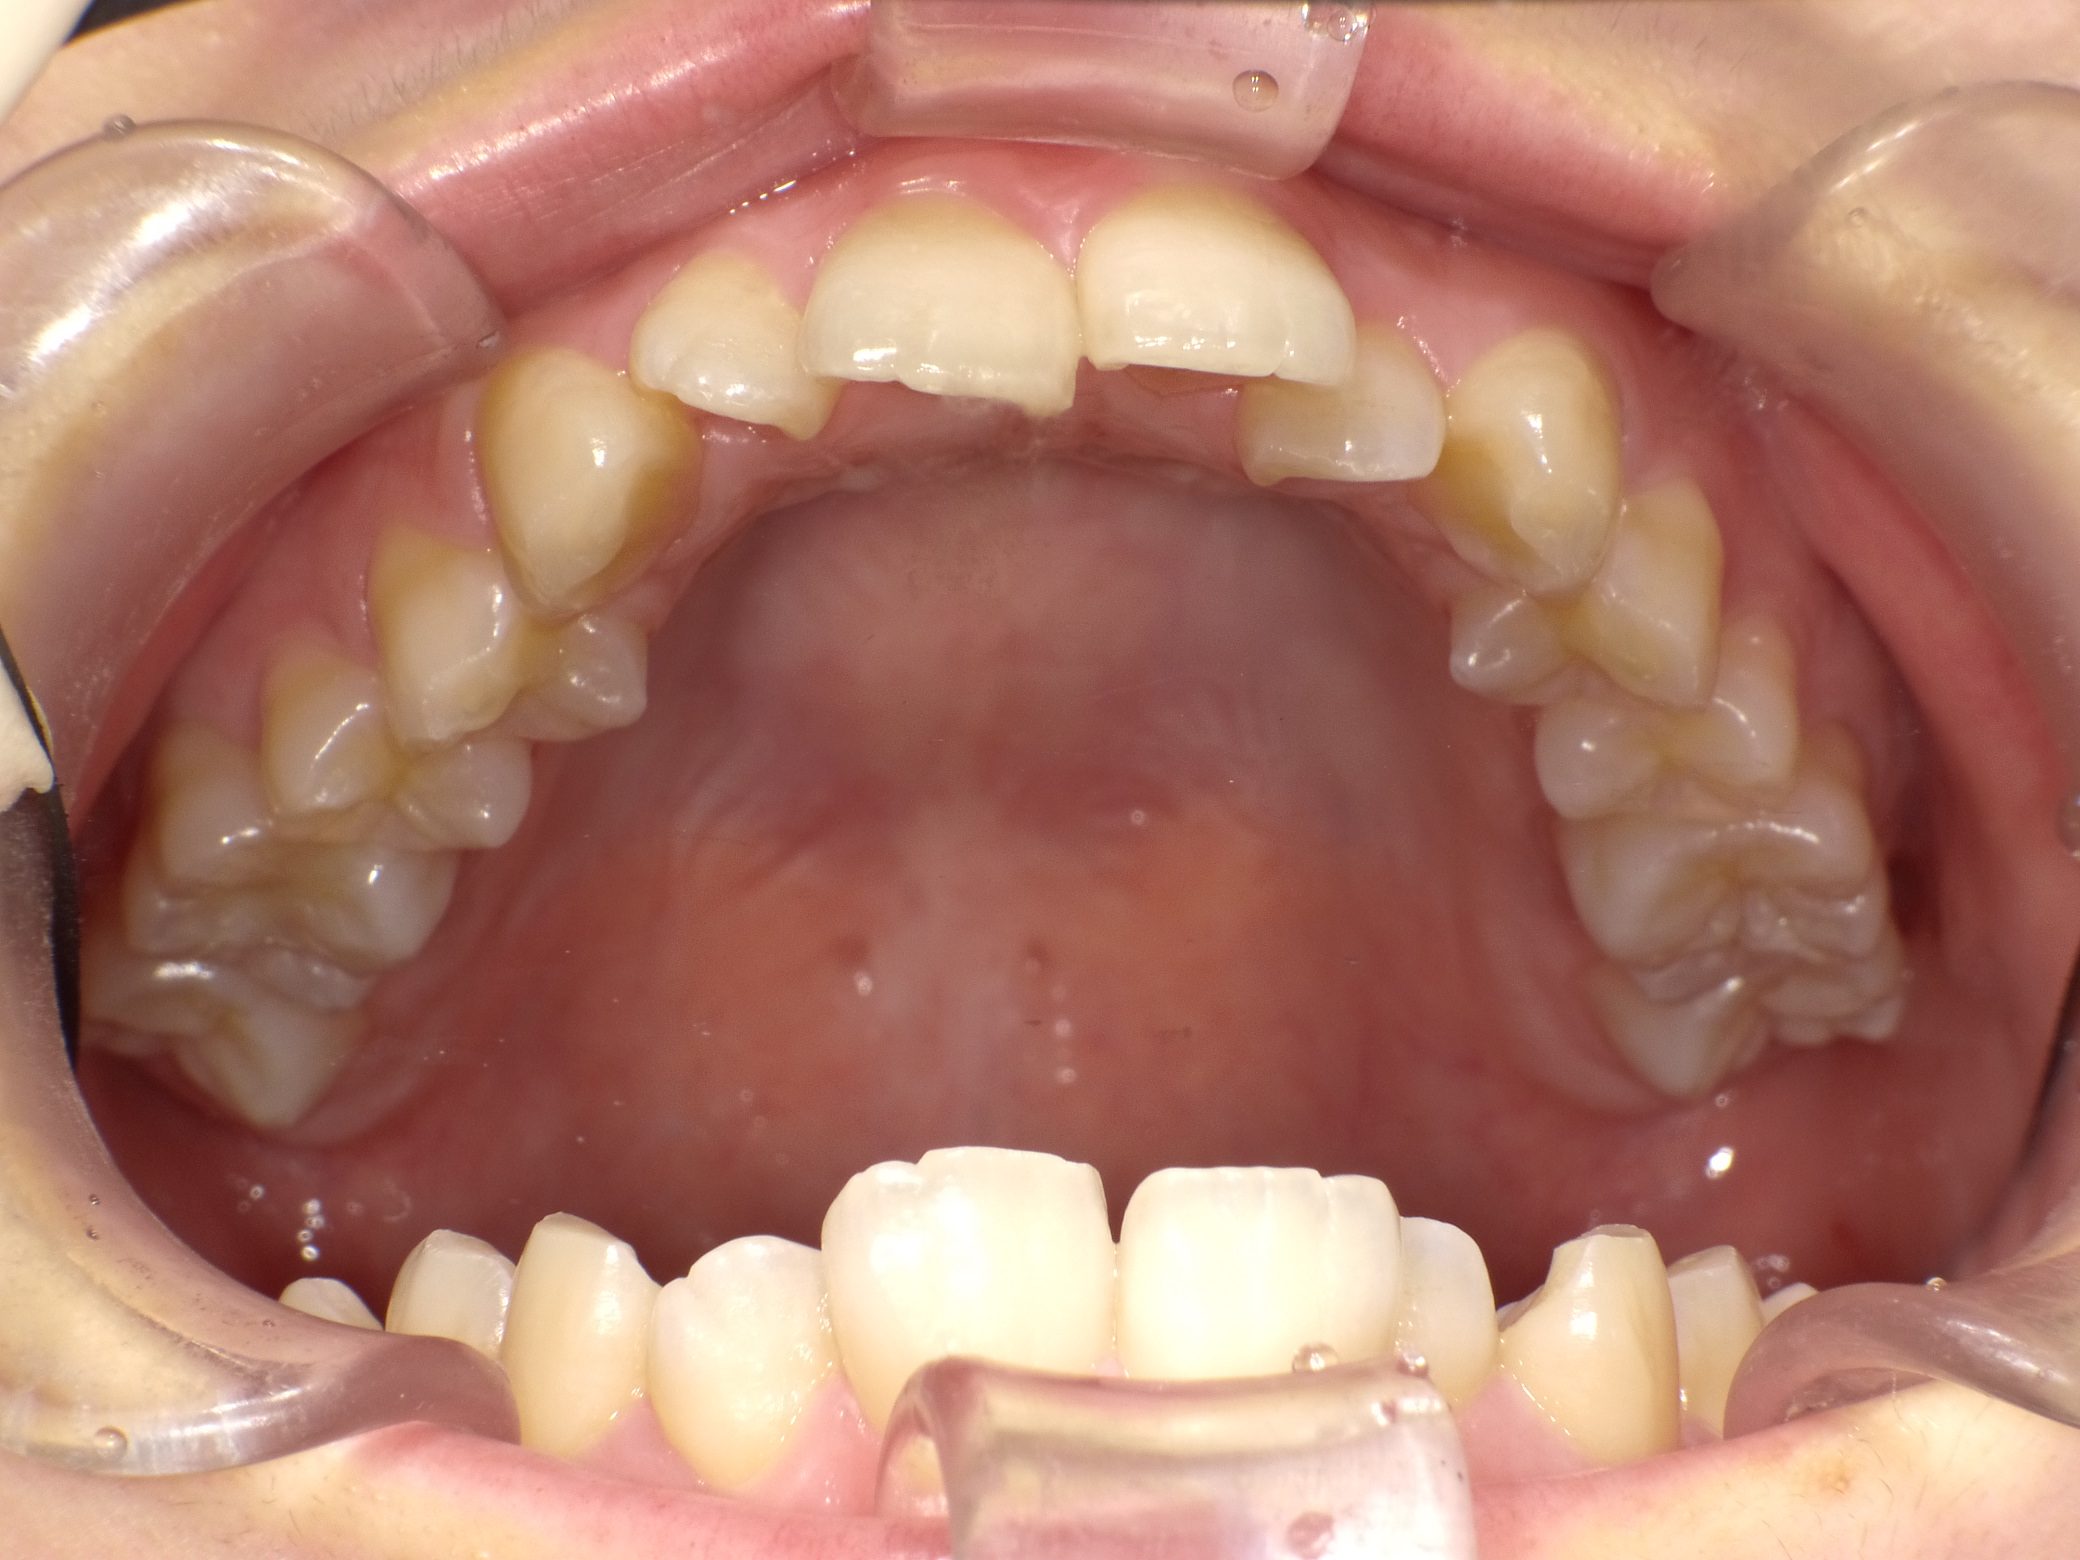

Before

After